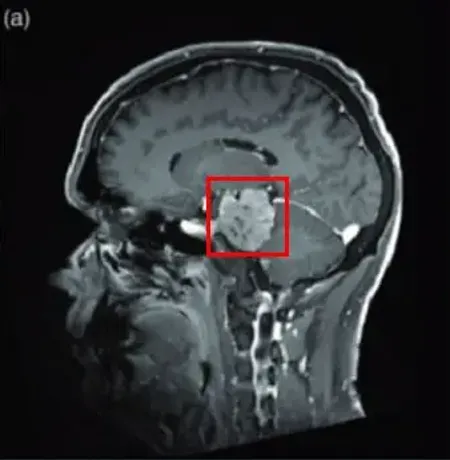

法国巴黎一位53岁男士,因三叉神经痛合并三叉神经感觉减退,在当地知名神经外科医院Lariboisiere医院,查出左侧巨大岩斜脑膜瘤(27立方厘米)。脑磁共振(MRI)显示可见明显的轴外肿瘤,岩斜向外扩张,对脑干有明显的挤压效应。经该院神经外科主席福教授主刀手术后,这个复杂位置的脑膜瘤得以完整切除,无神经功能损伤及相关的并发症。

图(a)为术前脑膜瘤影像图